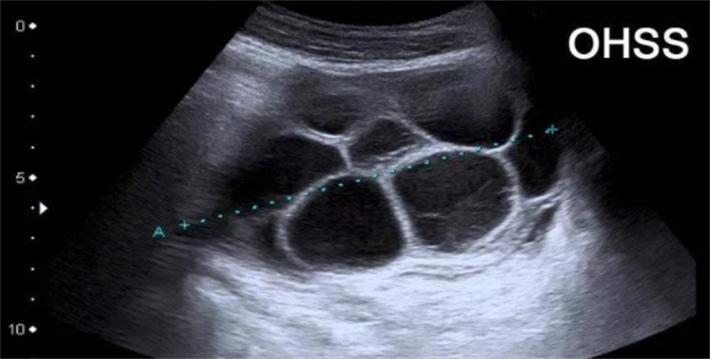

卵巢过度刺激综合症是在试管婴儿助孕中,由于促排卵药物的使用,导致卵巢对促性腺激素反应过度,可能出现卵巢增大、腹胀、胃肠道不适等症状。严重时,还可能导致血栓形成、肝肾功能损伤等危险情况。因此,了解并预防OHSS是试管婴儿过程中的重要一环。

在促排卵过程中,卵巢体积会显著增大,变得非常敏感和脆弱,卵巢扭转的风险会大大增加。扭转通常伴随着剧烈的腹痛、恶心和呕吐。此外,由于卵巢内充满了液体和卵泡,如果受到外力或自身压力的影响,还可能发生破裂出血等严重并发症。